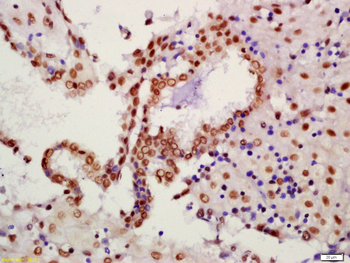

100 μl, 200 μl, 50 μl - LATS2 Rabbit Polyclonal Antibody [orb6306]Featured

IF, IHC-Fr, IHC-P, WB

Human, Mouse, Rat

Bovine, Canine, Equine, Gallus, Rabbit

Rabbit

Polyclonal

Unconjugated

100 μl, 200 μl, 50 μl - Featured